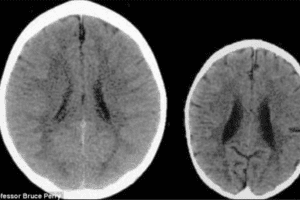

Bruce Perry, jefe del departamento de Psiquiatría del Hospital de Niños de Texas, compartió fotos comparativas de un escaneo cerebral de dos niños de 3 años de edad, en el cual se puede apreciar la diferencia atroz entre una y la otra.

Las fotos comparativas son entre la de un niño de 3 años, quien ha recibido amor y cuidado durante sus primeros años de vida (cerebro grande adecuado a la edad cronológica), y por otro lado el cerebro de un pequeño quien recibió maltrato infantil durante el periodo de esos tres años (foto del cerebro pequeño de la derecha).

El especialista afirma con sus propias palabras “estas imágenes ilustran el negativo impacto que la negligencia produce en el desarrollo del cerebro”, en otras palabras, el cerebro crece dos veces más lento que lo normal en estos casos.